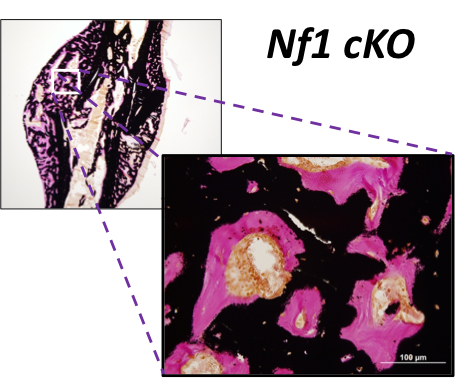

Role of Neurofibromin in the Bone Mesenchymal Lineage

By studying how Nf1 loss-of-function impacts the maturation and function of chondrocytes and osteoblasts, we seek to understand the etiology of the most problematic skeletal maladies associated with neurofibromatosis type 1 (NF1), which includes dystrophic scoliosis, tibia bowing and recalcitrant bone healing.